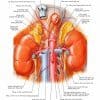

II. Giải phẫu

– Thận hình hạt đậu nằm phía sau ổ phúc mạc, 2 bên cột sống.

– Rốn thận chứa mạch máu ra-vào thận và niệu quản.

– Ngoài cùng là mạc thận, bản chất là mô liên kết, gồm 2 lá (trong và ngoài). Tiếp đến là lớp mỡ quanh thận, rồi đến bao thận và cuối cùng là nhu mô thận.

– Động mạch thận: thận được cấp máu bởi động mạch thận, tách ra từ động mạch chủ bụng. Động mạch thận phải đi phía sau tĩnh mạch chủ dưới. Động mạch thận vào thận qua rốn thận, sau đó chia làm nhiều nhánh – chia các động mạch liên thùy – chia thành nhiều động mạch cung.